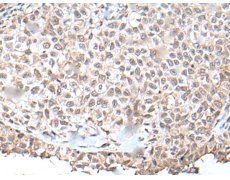

IHC positive control:

Human ovarian cancer and human tonsil

IHC Recommend dilution:

50-300